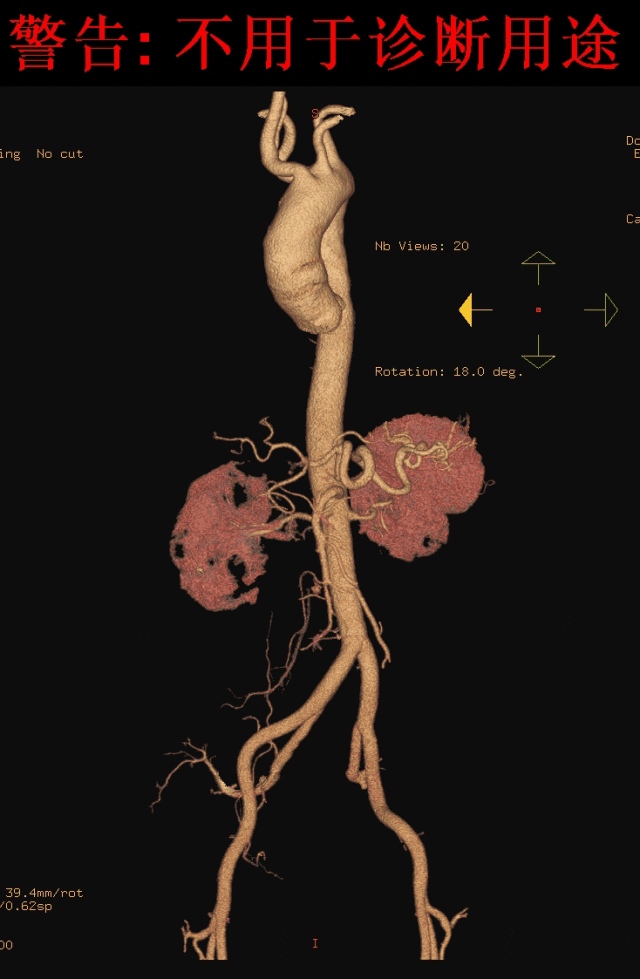

术后随访:

6个月后再次随访,CTA影像图显示血管形态良好,血管支架通畅。

术后造影复查,右侧迷走锁骨下动脉的烟囱支架角度平顺,血流通畅。

右锁骨下动脉置入Viabahn支架和Smart Control支架,左锁骨下动脉同样进行针刺开窗,最终造影情况良好。

手术结果良好,无任何内漏。